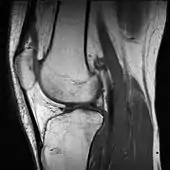

In addition, variants of false color such as pseudocolor, density slicing, and choropleths are used for information visualization of either data gathered by a single grayscale channel or data not depicting parts of the electromagnetic spectrum (e.g. elevation in relief maps or tissue types in magnetic resonance imaging).

A pseudocolor image (sometimes styled pseudo-color or pseudo color) is derived from a grayscale image by mapping each intensity value to a color according to a table or function.[11] Pseudo color is typically used when a single channel of data is available (e.g. temperature, elevation, soil composition, tissue type, and so on), in contrast to false color which is commonly used to display three channels of data.[4]

Depending on the table or function used and the choice of data sources, pseudocoloring may increase the information contents of the original image, for example adding geographic information, combining information obtained from infrared or ultra-violet light, or other sources like MRI scans.[13]